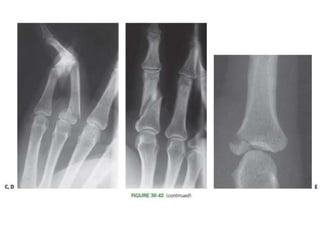

• #72 Fracture patterns appearing in P1 include (A) complete articular fractures of the head, (B) subcapital fractures with impingement in the volar plate recess

• #73 (C) transverse fractures of the shaft or base, (D) oblique fractures of the shaft, (E) articular fractures of the base.